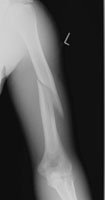

- Click on the image for a larger versionBAP radiograph of the humerus. The mildly displaced fracture is identified.